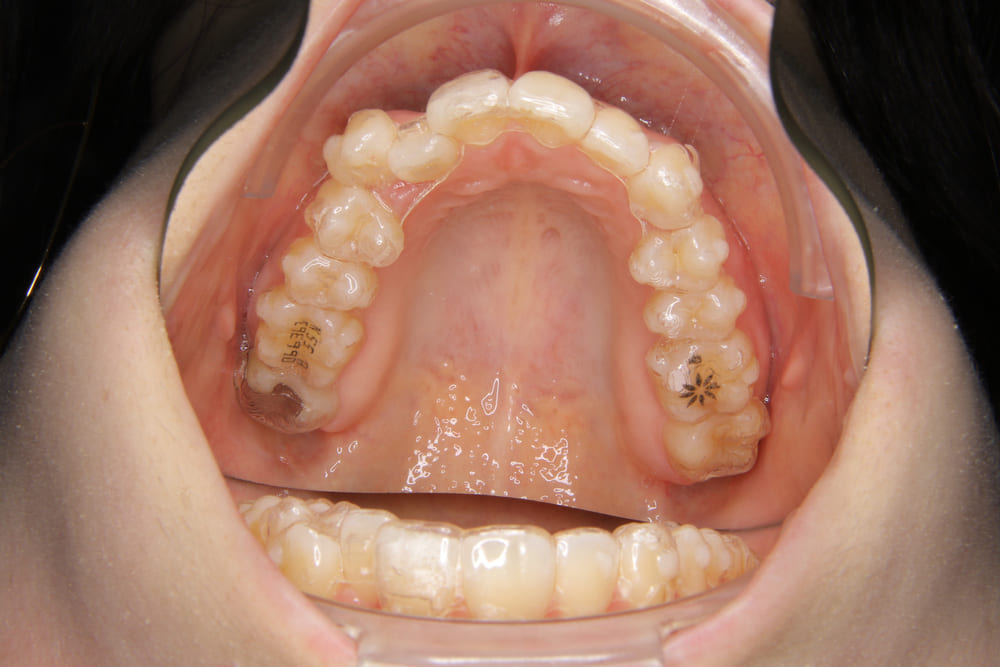

2精密検査

レントゲン撮影、口腔内写真・顔貌の写真撮影、口腔内スキャナー(iTeroなど)による精密な歯型採得など、治療計画の立案に必要なデータを収集します。

Q.虫歯や歯周病などの病気があっても、矯正できますか?

A. 最初の診断で虫歯や歯周病があった場合は、矯正を始める前にお口のトラブルを治療します。万が一、矯正中に虫歯ができてしまった場合は、矯正に影響が出ないように虫歯治療を行います。